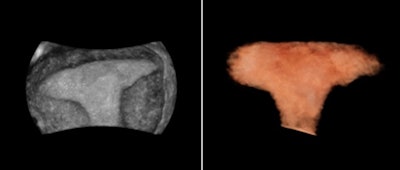

In gynecology, 3D ultrasounds can be helpful in many circumstances, including but not limited to evaluating the relationship of masses in the endometrial cavity, identifying uterine congenital anomalies and a thickened and/or heterogeneous endometrium, and evaluating the location of an intrauterine device and the integrity of the pelvic floor, according to Benacerraf and guidelines found in the 2014 American Institute of Ultrasound in Medicine (AIUM) practice parameter "Ultrasound of the Female Pelvis." Specifically, uterus malformations such as a bicornuate, or heart-shaped, uterus can be easily evaluated with 3D, Benacerraf said at the 2012 ISUOG meeting.

Uterus shape visualized with 3D thick-slice image (left) and 3D volume (right). All images courtesy of ContextVision.In reproductive medicine, the ovaries are measured to detect abnormalities. Ovarian size can be determined by measuring the ovary in three dimensions (width, length, and depth) on views in two orthogonal planes or by visualizing a 3D volume, according to the 2008 AIUM practice parameter "Ultrasound in Reproductive Medicine."